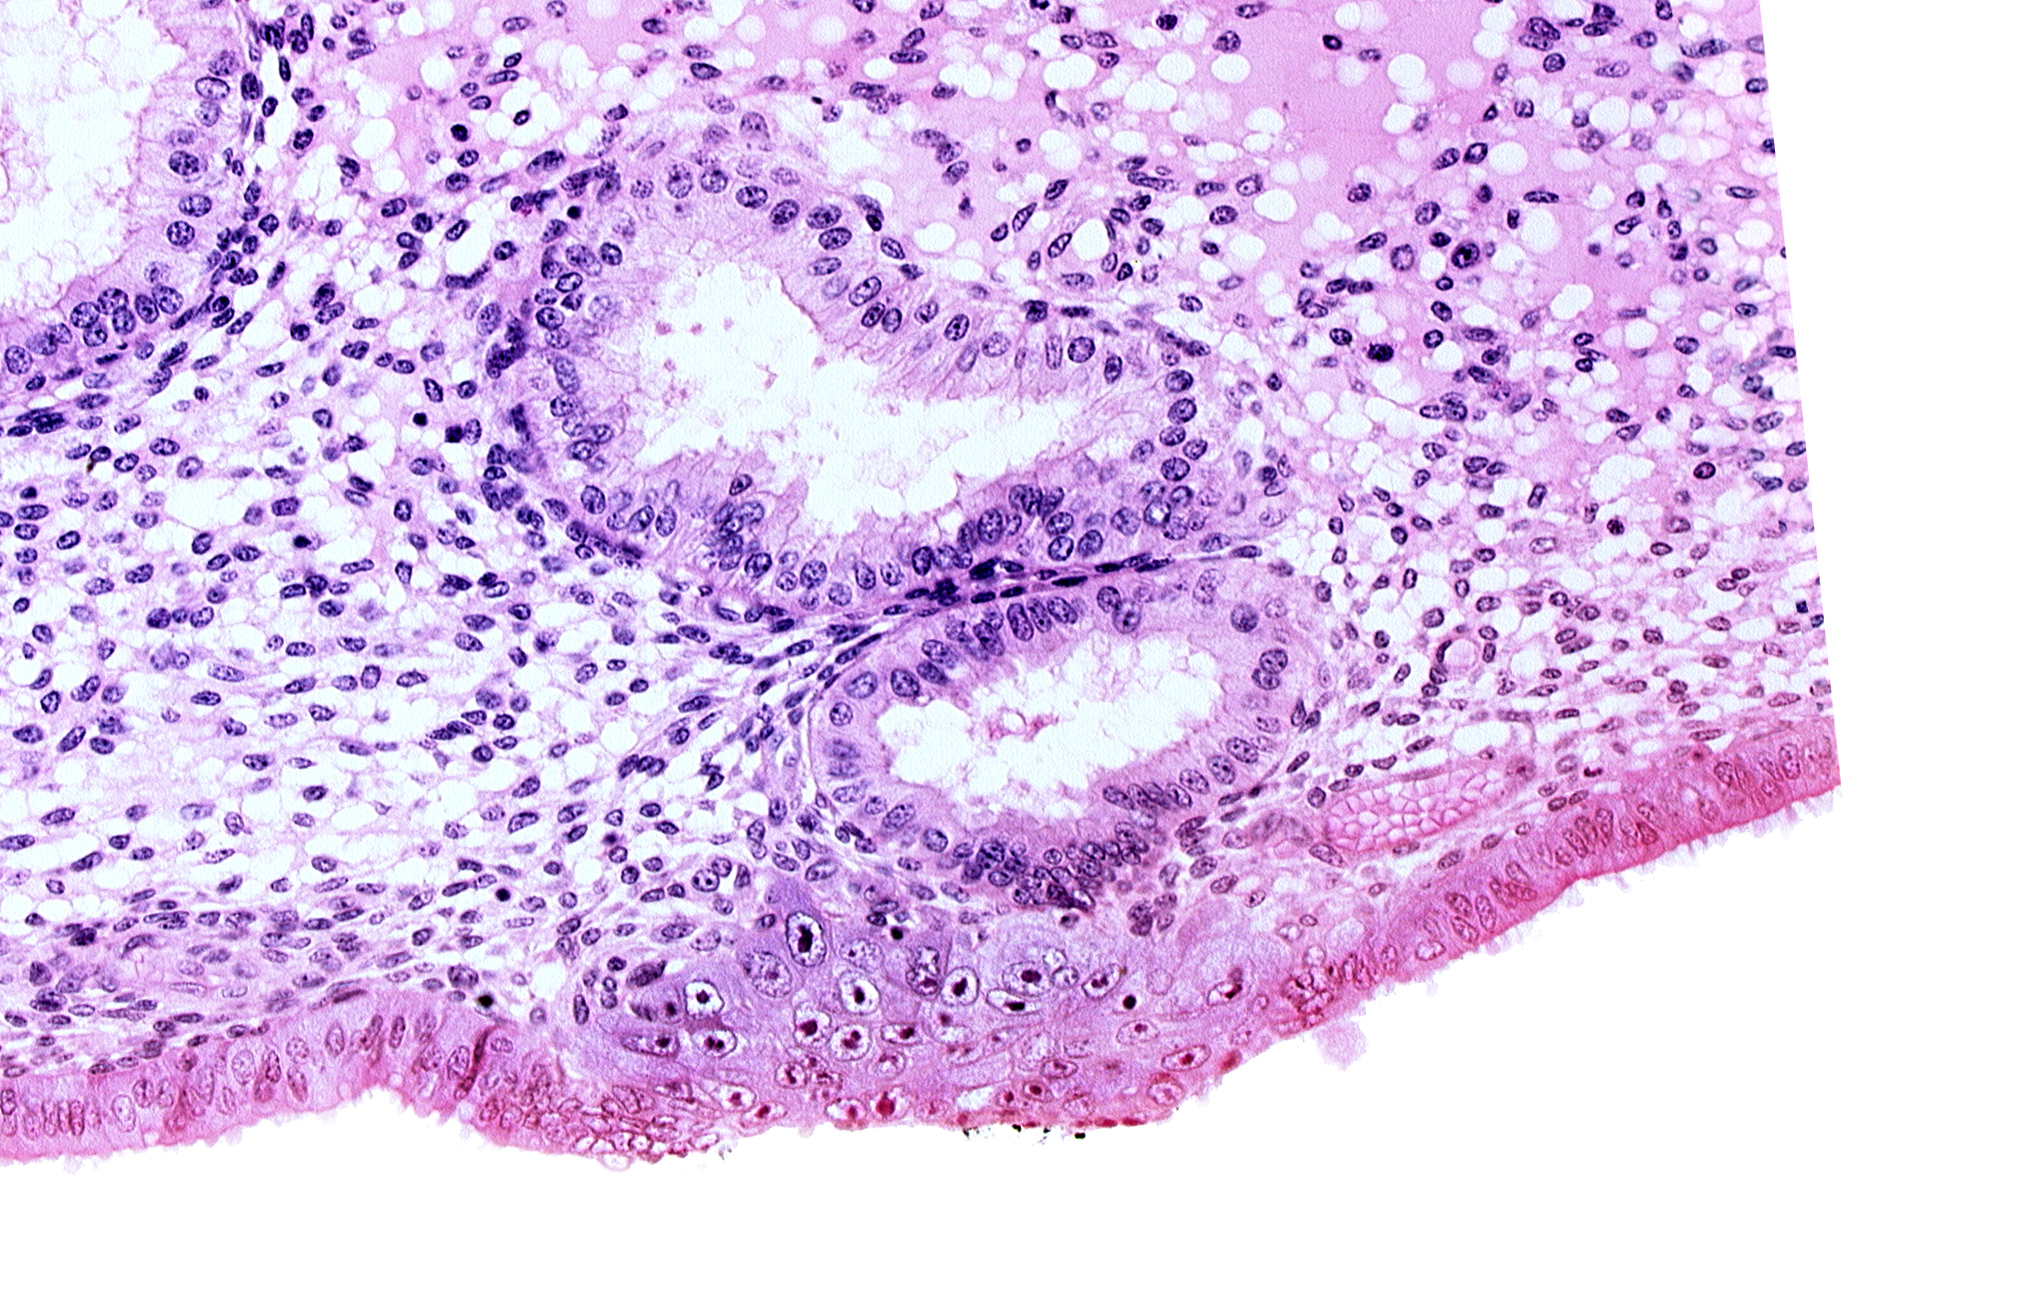

Carnegie Embryo #8020 | Location: 06-04-09

Keywords: disrupted endometrial epithelium, edematous endometrial stroma (decidua), endometrial epithelium, endometrial gland, solid syncytiotrophoblast, uterine cavity